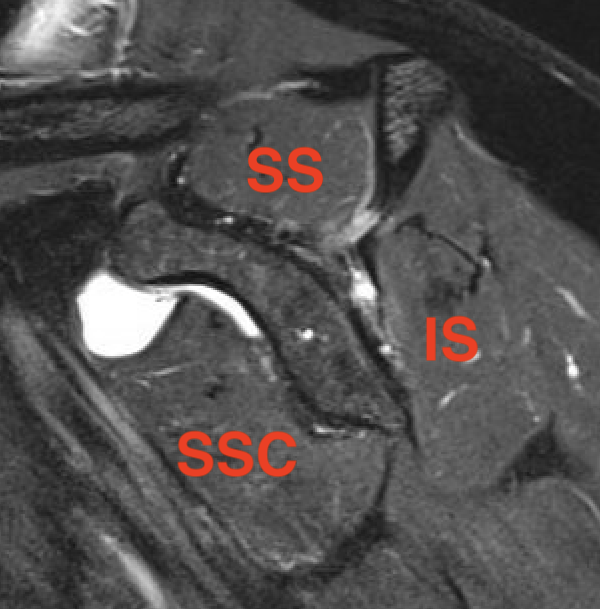

Goutallier classification

Amount of fatty degeneration in rotator cuff muscle belly on a T1 sagittal MRI

Stage 0: normal muscle

| Stage 1 | Stage 2 |

|---|---|

|

Some fatty streaks MRI shows some fatty streaks in supraspinatus |

More muscle than fat MRI shows grade 2 in supraspinatus |

|

|

| Stage 3 | Stage 4 |

|---|---|

|

Equal fat and muscle MRI demonstrates grade 3 supraspinatus and infraspinatus |

More fat than muscle MRI demonstrates grade 4 infraspinatus |